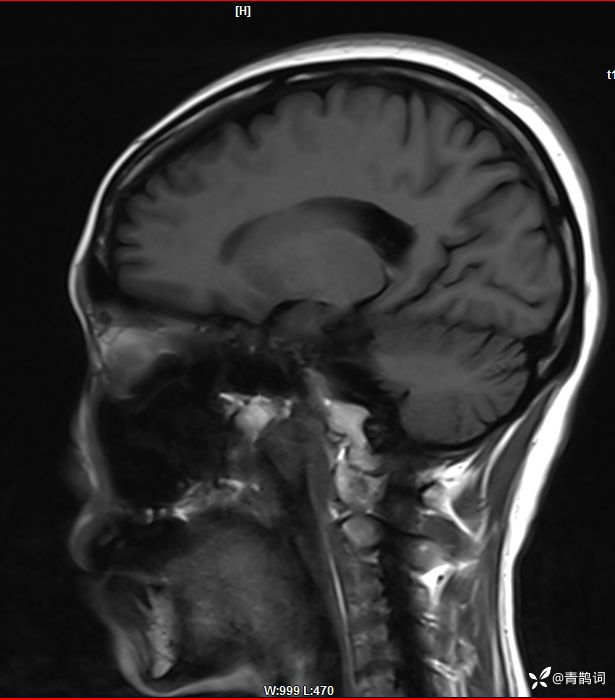

病例分享 | 45岁女患,7年的病史,结合影像学,如何诊断?

1、患者:女, 年龄:45岁

2、主诉:走路不稳渐加重7年,饮水呛咳伴头晕2年渐加重。

3、简要病史:患者于入院前7年出现走路不稳,表现为行走右偏,逐渐加重,易跌倒、不能自理;近2年出现饮水呛咳、吞咽困难及头晕;病程伴有耳鸣、反应迟钝,无恶心、呕吐。既往否认高血压、否认糖尿病、否认冠心病。

4、体格检查:体温36.0℃,脉搏80次/分,呼吸20次/分,血压140/70mmHg。查体:神清,构音障碍;眼球运动自如,双水平性眼震,左视时明显;双侧瞳孔等大同圆,左:右=3mm:3mm,对光反射灵敏;双侧额纹对称,双侧鼻唇沟对称;伸舌居中;四肢肌力4级,肌张力减低,四肢腱反射亢进,双侧Babinski征阳性;粗测感觉未见明显异常;四肢共济运动完成差,左侧为著;脑膜刺激征阴性。

入院后完善磁共振:

T1: